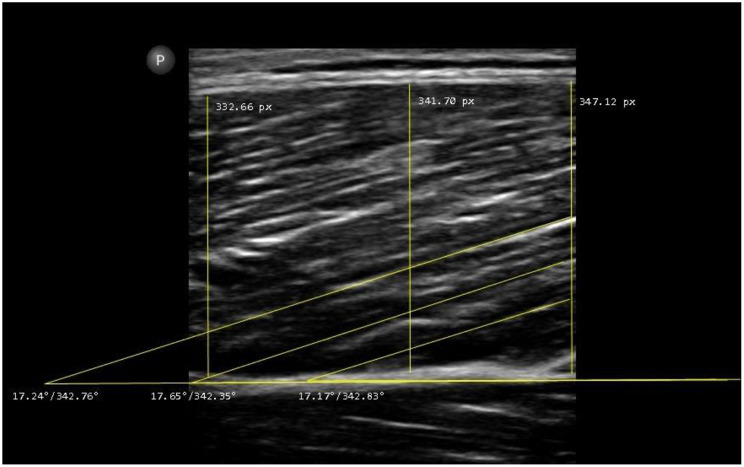

Structural muscle properties are critical in health and athletic settings, with magnetic resonance imaging considered the gold standard assessment procedure under static conditions due to its reliability and objectivity. Practical limitations, including cost and accessibility, have led to the increasing use of ultrasound as an alternative for skeletal muscle morphological parameters. However, ultrasound measurements are sensitive to evaluation conditions and assessor experience, which has not been sufficiently explored, yet. Therefore, this study investigated the influence of assessor experience on the reliability of ultrasound measurements. A double-blind design was used, involving an experienced assessor (> 12,000 images for several years) and multiple inexperienced assessors (< 100 images) to collect data from 39 recreationally active participants. Measurements of muscle architecture were conducted in the leg muscles over two consecutive days, generating 1,248 ultrasound images. Relative and absolute reliability were analyzed using intraclass correlation coefficients (ICCs), standard error of measurement, minimal detectable change, mean absolute error (MAE), mean absolute percentage error (MAPE) and Bland-Altman analyses. Relative reliability was good to excellent in all measurement spots and time-points for muscle thickness (ICC = 0.76-0.98) irrespective of assessor experience, except for the inter-day comparison for the gastrocnemius lateralis by the inexperienced assessors, (ICC = 0.58). The pennation angle assessment ranged from insufficient to excellent reliability (ICC = 0.18-0.94) and experience contributed greatly to better results. The random error for the inexperienced assessors was reflected in two- to three-times higher MAEs/MAPEs and limits of agreement in the Bland-Altman analyses, respectively. The findings emphasize the importance of experience and standardization in achieving reliable ultrasound data, particularly for (a) sensitive parameters like the pennation angle and/or (b) inter-day, intra-subject comparisons.